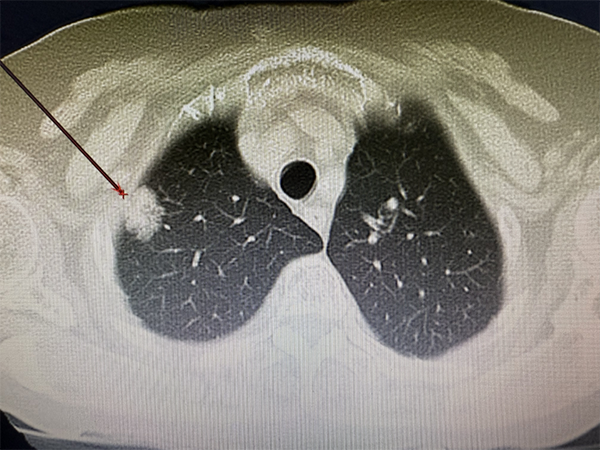

治疗前CT

家住沈阳市铁西区的张奶奶,8月下旬在市五院胸外科门诊做双肺CT常规检查时,发现左肺上叶有一直径2.1厘米的实性结节,该结节形态不规则,边缘呈毛刺状,是典型的肺癌影像学改变。手术是这类病症的首选治疗方案,但张奶奶年事已高,对全麻手术十分抗拒,加之儿女远在国外,家里只有她和老伴两个人,她不仅要照料自己,还要承担起照顾生活无法完全自理的老伴的重任,因此希望能有其他治疗办法。胸外科团队经过多轮病例分析和方案推演,最终为她定制了局麻下微创消融术的治疗方案。